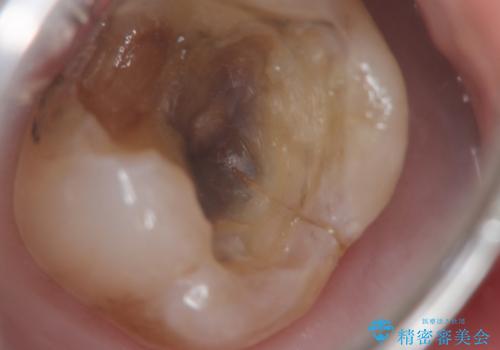

- 奥歯が咬むと痛い、熱いものがしみることを主訴に来院された患者様です。

奥歯(左上7)のメタルインレー(銀の詰め物)を除去し精査したところ、奥歯はわれていました。

根尖近くまで深くヒビが入っており保存不可能な状態でした。